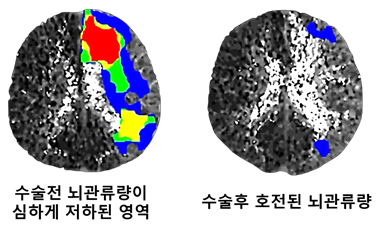

혈전제거술이 불가능하거나 실패한 급성 뇌경색 환자에게 응급 뇌혈관문합수술의 효과성과 안전성을 영상학적으로 뇌혈류의 정량적인 분석을 통해 입증된 연구도 있다.

예전에는 “4.5시간 지나면 무조건 늦었다”라고 했지만, 지금은 뇌영상 기술(MRI, CT perfusion 등)의 발달로 시간이 아니라 뇌 상태를 기준으로 치료 판단을 한다.

- 뇌 MRI 또는 CT로 펜브라(parenchymal penumbra), 즉 죽지 않고 회복 가능한 뇌 조직이 남아 있는지를 판단한 후 시행한다.

- 시간이 지나더라도 구조적으로 살아있는 뇌 조직이 있다면 치료 효과를 볼 수 있다.